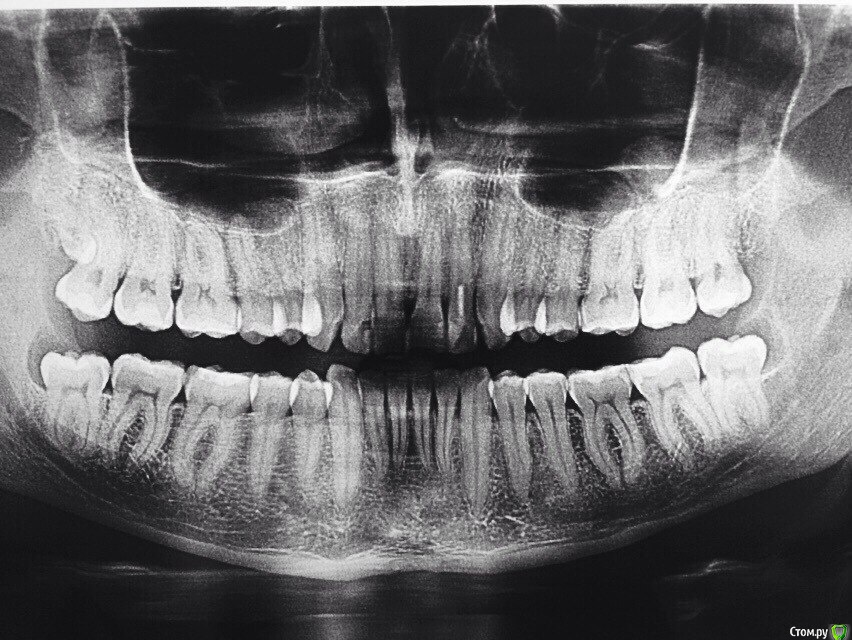

kamranchick Опубликовано 12 июля, 2015 Поделиться Опубликовано 12 июля, 2015 (изменено) Добрый день Уважаемые друзья)имеются следующие панорамники. хотелось бы посоветоваться с Вами.1, пациент обратился на затрудненное открывание рта, хотя на ширину 3 пальцев открывает рот, отправил на панорамный снимок и увидел суть проблемы. Боли начались неделю назад, боли только при открывании. слизистая слегка гиперемирована. Гигиена у пациента отличная, редко такое видел, 28 лет. у меня 2 плана, либо удаление всех 8ых зубов, либо оставить ихсмущает тот факт что пациент является профессиональным боксером, не поспособствует удаление нижних 8 зубов к перелому челюсти? и еще смущает факт очень мелкое преддверие полости рта, щеку просто не оттянуть))какие будут рекомендации и совета, из назначений было только употребление Намесил 1пак в день и полоскание мирамистином2. пациент обратился с целью протезирования, проблема в том, что он работает вахтовым методом, и постоянно в разных городах, можете ли подсказать системы имплантов которые ему установили, и какую конструкцию можно ему предложить(ибо я ортопед) от синус лифтинга отказывается, пациенту 55 лет, гигиена удовлетворительная. а так же обратно-перекрестный прикус Изменено 12 июля, 2015 пользователем kamranchick Ссылка на комментарий

Kovalov Igor Опубликовано 17 июля, 2015 Поделиться Опубликовано 17 июля, 2015 Дистопия и ретенция зубов наоборот способствует прохождению линии перелома челюсти, так сказать слабое место. Но у этого боксёра все зубы в ряду и скорее всего в прикусе. Ради профилактики можно и удалить их ... С капой перелом челюсти мало вероятен ... Ссылка на комментарий